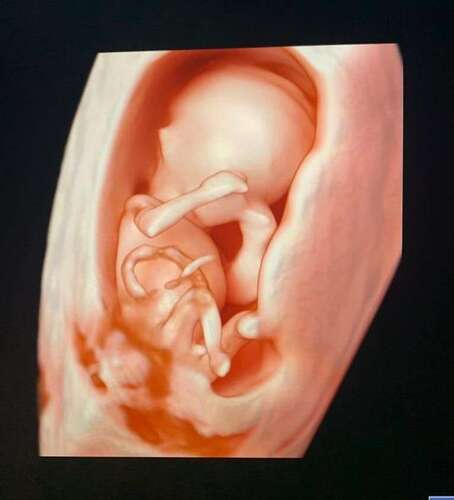

Kijk eens wat ze in t ziekenhuis voor elkaar hebben gekregen! Een hele mooie 3d echo met 13 weken!